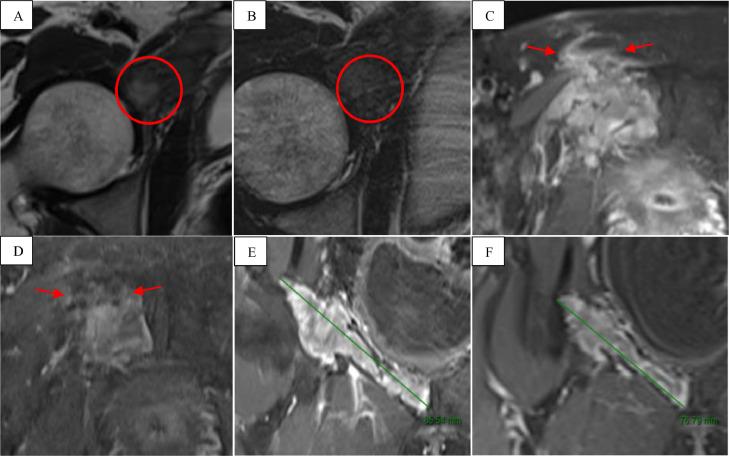

经动脉注射阿霉素洗脱微球栓塞术治疗耻骨区硬纤维瘤病

Transarterial doxorubicin-eluting beads embolization for the treatment of desmoid fibromatosis in the pubic region.

Desmoid fibromatosis (DFs) is rare, low-grade neoplasm. Although it poses no risk of metastasis, DFs exhibits a range of clinical manifestations characterized by local infiltrative growth tendencies and a propensity for recurrence. Despite its nonmalignant nature, DFs can be highly debilitating and occasionally life-threatening, causing severe pain and functional limitations. Traditionally, surgery served as the conventional primary treatment approach; nevertheless, a recent shift in paradigm towards a more conservative management has emerged, accompanied by efforts to standardize the strategy among clinicians. Systemic doxorubicin has been demonstrated to be effective in treating DFs; however, it carries potential risks of adverse effects on the cardiovascular, digestive, and hematologic systems. The novel intravascular intervention employing drug-eluting beads loaded with doxorubicin represents an effective treatment for DFs, optimizing drug delivery to the target lesion and reducing systemic toxicity. In this article, we present a rare case of DFs in the right pubic region treated with transarterial doxorubicin-eluting beads embolization.

摘要

韧带样型纤维瘤病(DFs)是一种罕见的低度恶性肿瘤。尽管它没有转移风险,但DFs表现出一系列临床表现,其特征为局部浸润性生长倾向和复发倾向。尽管DFs本质上并非恶性,但它可能极具致残性,偶尔还会危及生命,导致严重疼痛和功能受限。传统上,手术是常规的主要治疗方法;然而,最近出现了向更保守治疗模式的转变,同时临床医生也在努力使治疗策略标准化。已证明全身使用阿霉素对治疗DFs有效;然而,它对心血管、消化和血液系统存在潜在的不良反应风险。采用载有阿霉素的药物洗脱微球的新型血管内介入治疗是DFs的一种有效治疗方法,可优化药物向靶病变的递送并降低全身毒性。在本文中,我们介绍了一例经动脉阿霉素洗脱微球栓塞治疗的右侧耻骨区罕见DFs病例。